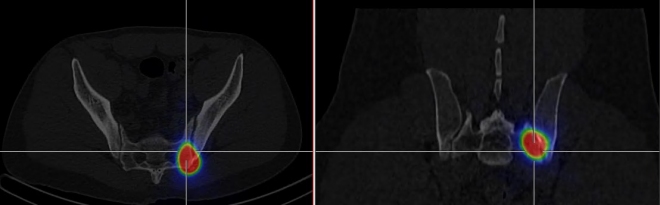

Následně provedena verifikační scintigrafie (obr.4) k posouzení distribuce RF (s využitím spektra brzdného záření). Distribuce RF pro RSO odpovídá rozsahu prokázané synovialitidy.

/ Obr.4.: SPECT/CT distribuční scintigrafie v axiálním a koronárním řezu - RF v levém SI skloubení.